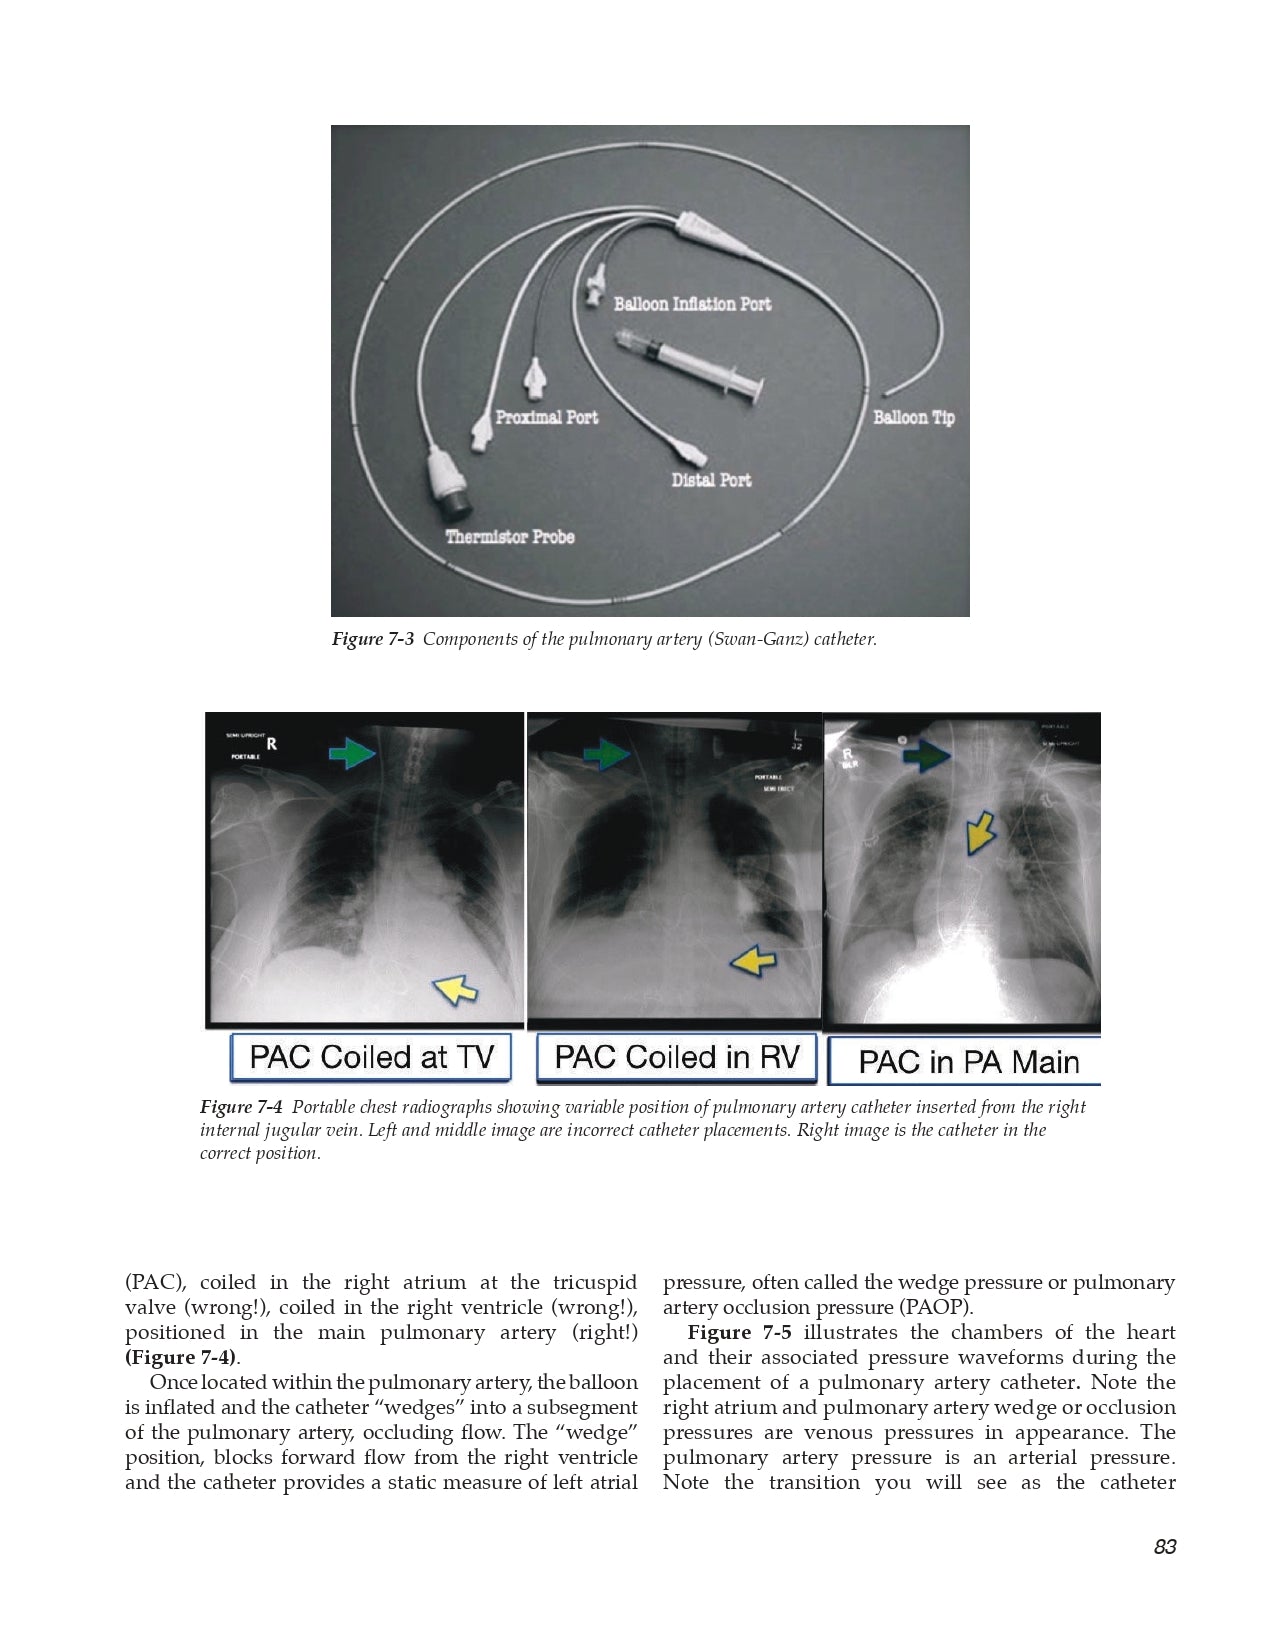

7.3 Vascular Pressures and the Pulmonary Artery Catheter